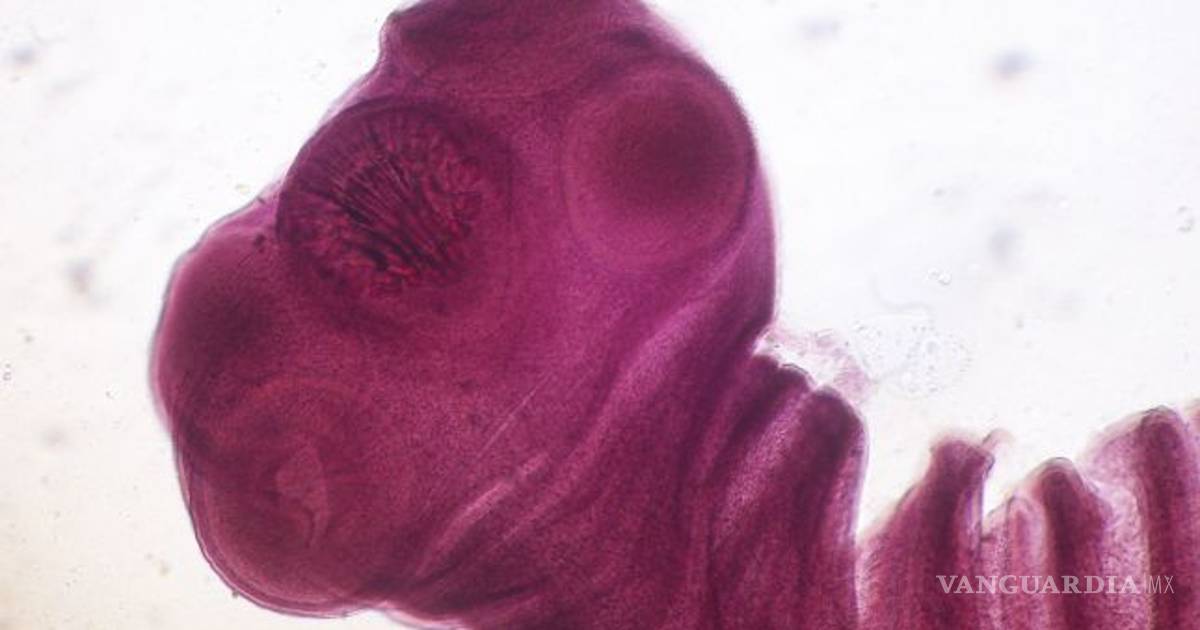

China. El Sr. Wang, un hombre chino, ha estado compartiendo durante 15 años su cerebro con una tenia, también conocida como solitaria, sin saberlo. Ahora lo han operado y le han sacado el insecto de su cabeza.

El hombre fue operado a finales de octubre, en un centro médico de la provincia de Guangdong (China). El insecto medía 12 centímetros y se estaba comiendo el tejido de su cerebro.

Según el neurocirujano que ha dirigido la operación, Gu Youming, si no se hubiera detectado el parásito en el cerebro del paciente y se le hubiera extraído, podría haber tenido graves consecuencias. La tenia se habría seguido comiendo la masa cerebral del hombre, y él se podría haber quedado paralizado o, incluso, morir.

Además, el doctor ha señalado que la intervención, que ha durado dos horas, era muy importante para sacar el insecto entero: "Si hubiera quedado alguna parte en el cerebro, habría vuelto a crecer", asegura.

Caracoles fritos, la causa

Después de la intervención, Wang ha recordado que el 2004 era aficionado a comer caracoles de río fritos con su cabeza. Un año después, en el 2005, asegura haber empezado a sentir los dolores, las náuseas, pinchazos en los brazos y las piernas y convulsiones.

El médico sospecha que el paciente se contagió con la carne del caracol, que quizás estaba poco cocida, o con algún otro animal exótico.